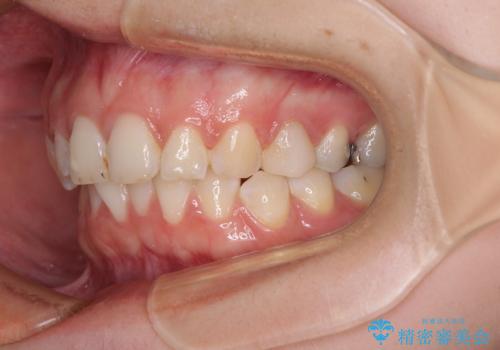

インビザラインでの矯正治療を希望されていましたが、奥歯の咬み合わせがインビザライン単独では改善困難と判断されたので、補助装置を併用することとしました。

まずは裏側の装置やワイヤー矯正を用いて歯列幅の狭い上顎を側方に拡大しつつ全体を後方に移動させ、その後インビザラインにて歯列を整えることとしました。

奥歯の咬み合わせの改善は、インビザライン単独では達成しきれないことがあるため、ワイヤー矯正などの補助装置を併用する場合があります。

インビザライン単独の場合と比べ、治療結果は大きく異なります。